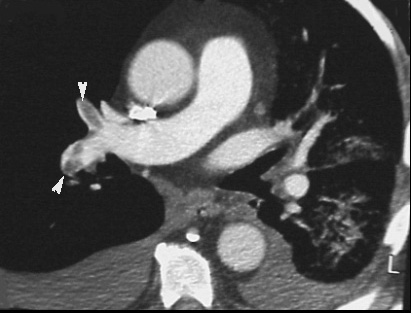

CT Angiogram Showing Filling Defects Consistent With PE

Patient had a low probability lung scan. Clinically there was high index of suspicion for pulmonary embolism.